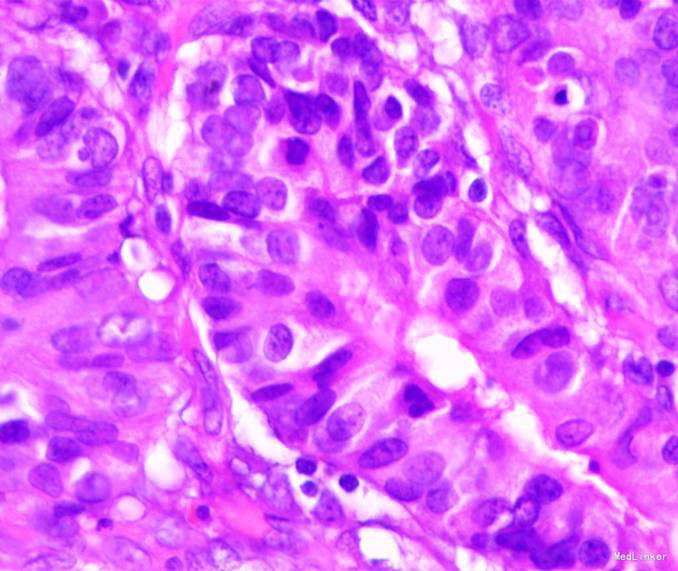

随访:出院后2周,电话随访患者,一般情况良好,无不适主诉。 讨论:该患者胃镜见一胃窦前壁粘膜隆起,表面粘膜粗糙,病理示:慢性萎缩性胃炎,伴部分腺体中重度不典型增生,局灶重度不典型增生,超声胃镜病灶未突破粘膜下层,有胃ESD手术指征,故行全麻下胃ESD术。术后病理:胃窦前壁肿瘤:腺上皮高级别上皮同瘤,部分癌变,病变大小1.5*1.1*0.3cm,基底及切缘未见癌。说明手术成功,切缘及基底均无肿瘤侵及。对于早癌患者我们完全可以通过采用ESD方法治愈患者,胃镜下切除早癌较腹腔镜创伤更小。我和患者解释时是这样说的:腹腔镜是微创,而我们内镜下ESD则是微微创。